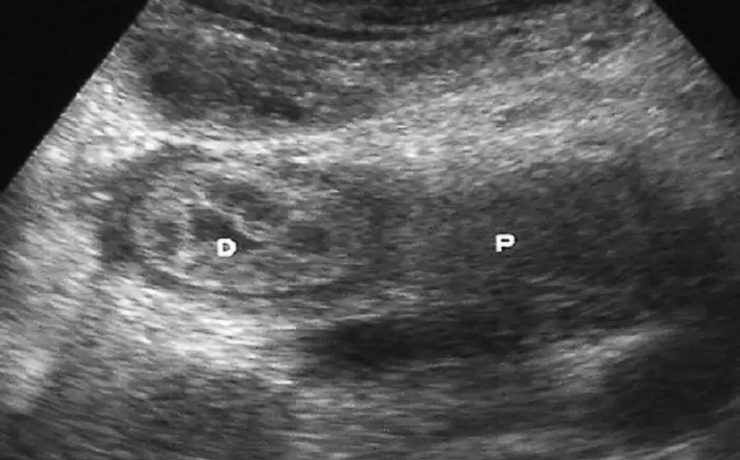

En este estudio se analiza la utilidad del ultrasonido en el estudio de la paciente estéril, específicamente con ultrasonido con aplicación de doppler, de Power doppler y la ecografía 3D para analizar los cambios cualitativos y cuantitativos que se observan en la irrigación del ovario en pacientes estériles, en pacientes